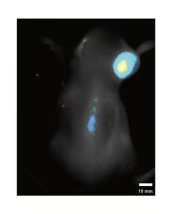

针对这些科研痛点,灵赋拓普生物基于成熟的动物实验平台,全新推出近红外二区(NIR-II)荧光活体成像服务,为您提供强大的在体观测能力,打破传统成像技术的局限。

传统荧光成像技术(可见光及近红外一区)受生物组织吸收和散射作用强的限制,存在成像深度浅、空间分辨率低、生物自发荧光干扰强等问题,难以满足活体深层组织“可视化”的需求。近红外二区荧光成像(900-1700 nm)是近年来迅速发展的新型成像技术,被誉为“下一代荧光影像技术”

肿瘤检测与导航:精准定位肿瘤边界,辅助手术导航

干细胞追踪与脏器成像:实时观测细胞迁移与组织损伤